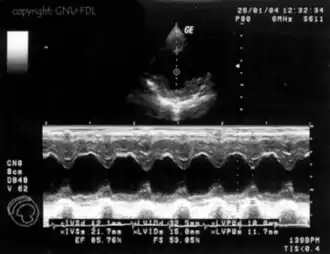

Um plot da intensidade do eco versus o tempo é chamado um scan A. Para formar uma imagem bidimensional, é necessário scanear em muitas direções (colunas da planilha) diferentes. Em um scan B, o brilho da tela corresponde à intensidade do eco, plotado versus posição no corpo no plano do escaneamento. O transdutor do scan B envia um feixe estreito dentro do corpo. A intensidade do eco determina a cor que a célula vai ter (branco para um eco forte, preto para um muito fraco, e graduações de cinza para as intensidades intermédias). Quando ocorre a transição entre dois meios com grande diferença de impedâncias, maior será a intensidade do eco e, desse modo, mais intensa (branca) será a imagem gerada.

Outros métodos de imagem de ultrassom incluem movimento ou modo M, que pode ser usado para observar o batimento do coração como uma função do tempo.